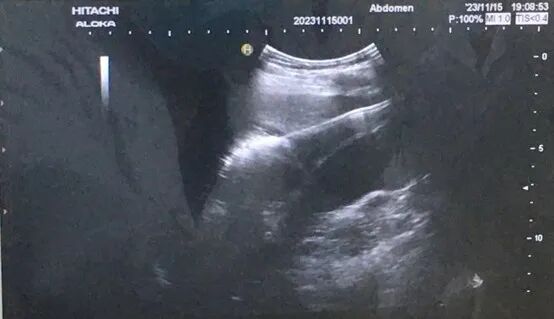

患者王先生,因酒精肝、肝硬化来我院住院治疗,住院期间发现肝S4低回声占位,考虑肝癌可能。

经多科讨论及研究后,经家属同意后,行超声引导下肝右叶肿瘤穿刺活检术及微波消融术,手术在南方医科大学南方医院吴凤林教授为技术指导下,功能科主任黄亮、医生严家伟、护士陈桃配合操作下。整个手术操作时间30分钟,过程顺利,术中及术后无明显疼痛。

(术中)

肝癌的微创消融治疗是在超声或者CT的引导下,将针形器具通过皮肤插入到肿瘤的局部,通过射频或微波等能量形式使针形器具前端发热,导致局部的温度增加。当温度增加到一定程度,并持续一定的时间之后,就会造成针尖的组织坏死。当坏死的范围覆盖整个肿瘤,就达到了局部灭活肿瘤组织的目的。